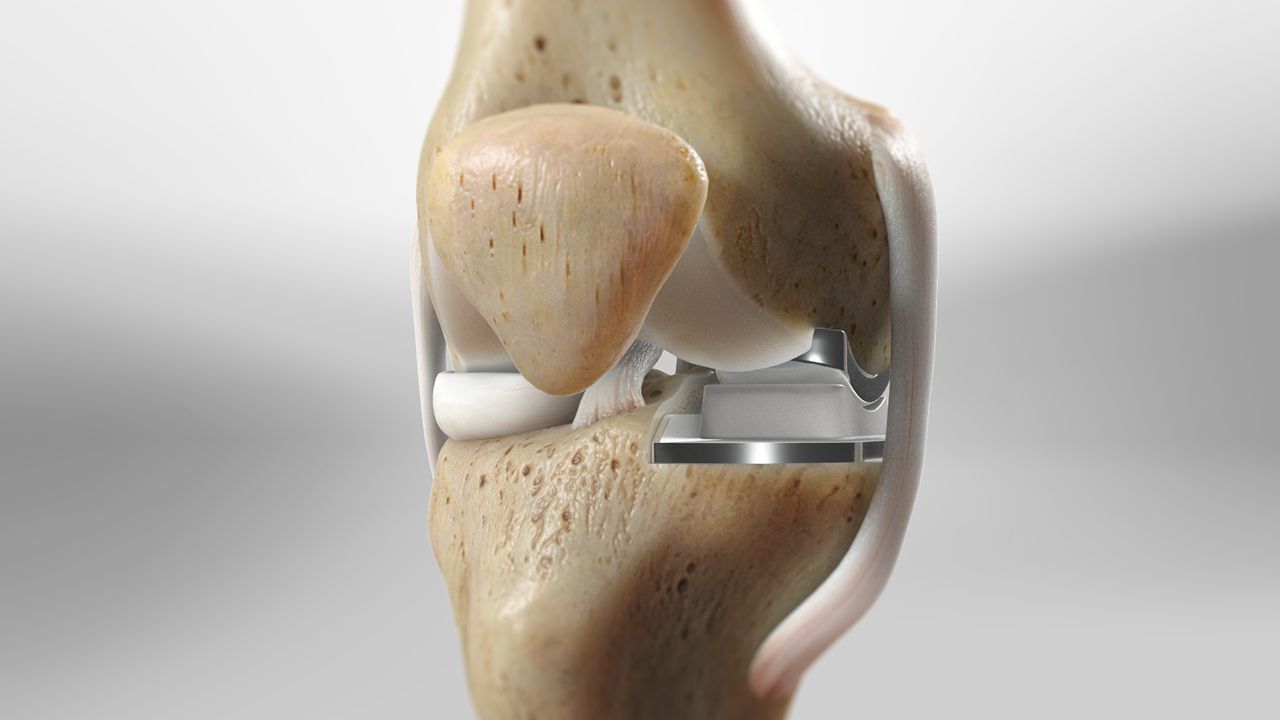

Total knee replacement, also known as total knee arthroplasty, is a surgical procedure designed to relieve pain and restore function in severely diseased knee joints. This procedure is typically recommended for patients suffering from severe arthritis or significant knee injuries that have not responded to conservative treatments such as medications, physical therapy, or less invasive surgeries. The knee joint, which is the largest joint in the body, is composed of the lower end of the thighbone (femur), the upper end of the shinbone (tibia), and the kneecap (patella). In a healthy knee, these bones are cushioned by cartilage, which allows for smooth and pain-free movement. However, in cases of severe arthritis, this cartilage wears away, leading to bone-on-bone contact, pain, and reduced mobility.

During a total knee replacement surgery, the damaged bone and cartilage are removed from the knee joint and replaced with artificial components. These components typically include a metal femoral component, a metal and plastic tibial component, and a plastic patellar component. The artificial parts are designed to mimic the natural movement of the knee, allowing for improved function and reduced pain. The surgery involves making an incision over the knee, removing the damaged tissue, and securing the new components to the bone using specialized cement or other fixation methods.